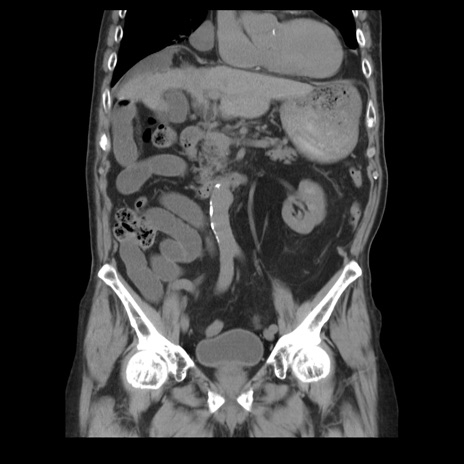

症例21(冠状断像)

【症例】70歳代男性

【主訴】腹痛

【現病歴】肝硬変・肝細胞癌にてかかりつけの方。約9時間前に食後より腹痛出現。症状が徐々に増悪し、嘔吐出現したため来院。

【既往歴】肝硬変、肝細胞癌(RFA、TACE後)

【身体所見】意識清明、表情苦悶様、BT 36℃、BP 129/78mmHg、P 88bpm、SpO2 97%(RA)、右上腹部から心窩部にかけて圧痛あり、反跳痛なし、筋性防御あり。

【データ】WBC 5800、CRP 0.16